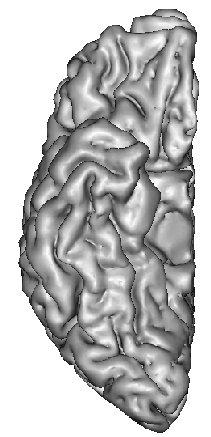

The resulting grey/white interface can be converted into a mesh endowed with the spherical topology, which will be inflated by some other Brainvisa treatments for visualization purpose (Ana Inflate Cortical Surface):

A dilation of this interface towards the outer brain edges may lead to nice 3D rendering of the cortical surface, which are easy to read because the folds are opened (Ana Get Opened Hemi Surface) :